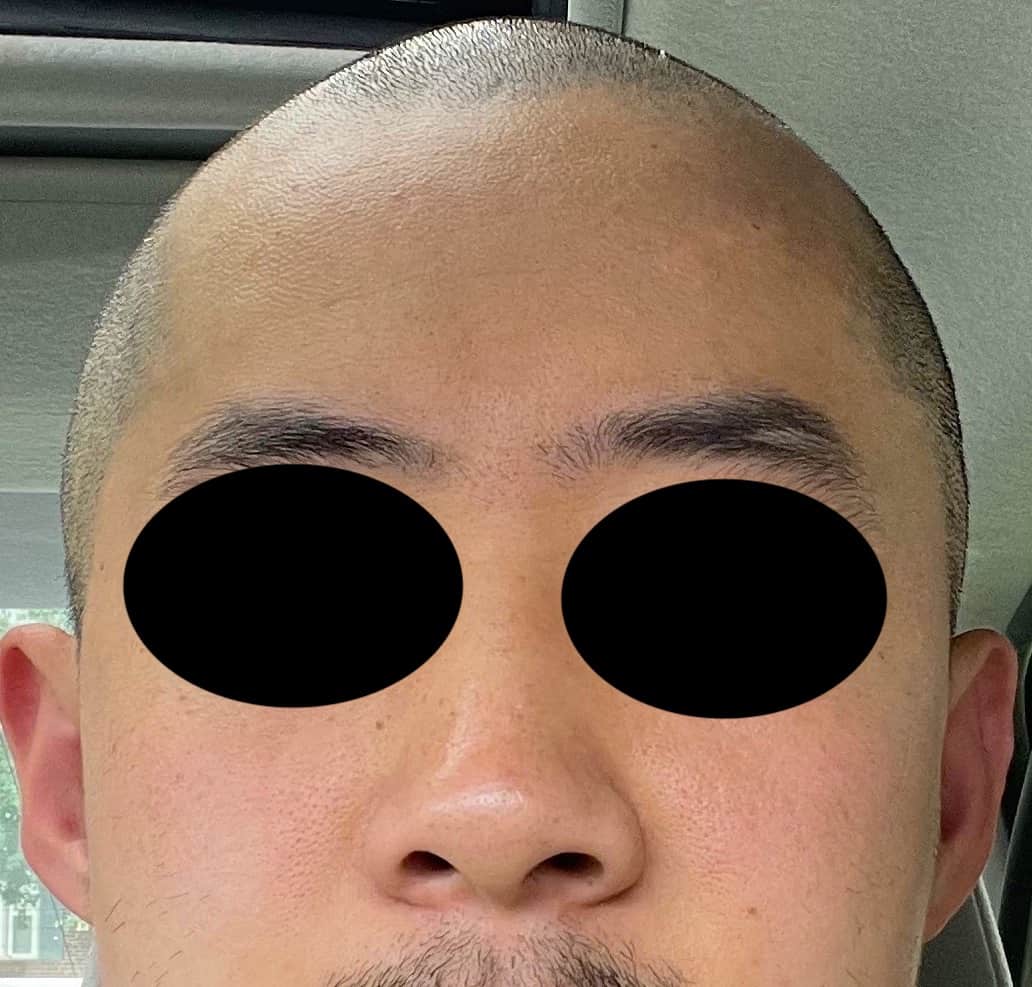

Patient 100

Desire for reshaping of an asymmetric flat back of the head in a shaved head male.

A combined back of the head reshaping procedure was done with a custom skull implant, sagittal ridge reduction and a right temporal muscle reduction.

Desire for reshaping of an asymmetric flat back of the head in a shaved head male.

A combined back of the head reshaping procedure was done with a custom skull implant, sagittal ridge reduction and a right temporal muscle reduction.